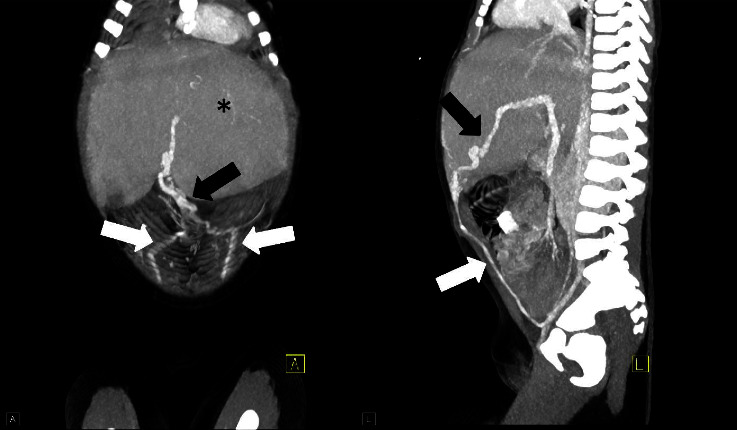

Congenital hepatic fibrosis is a rare, autosomal recessive, fibro-polycystic disease resulting from ductal plate malformation, leading to proliferation and fibrosis of bile ducts. Progressive hepatic fibrosis leads to portal hypertension and varices which can present with life threatening gastrointestinal hemorrhage. We report a case of congenital hepatic fibrosis in a 2-year-old child who presented with 8 days of fever without any significant medical history or physical examination findings.